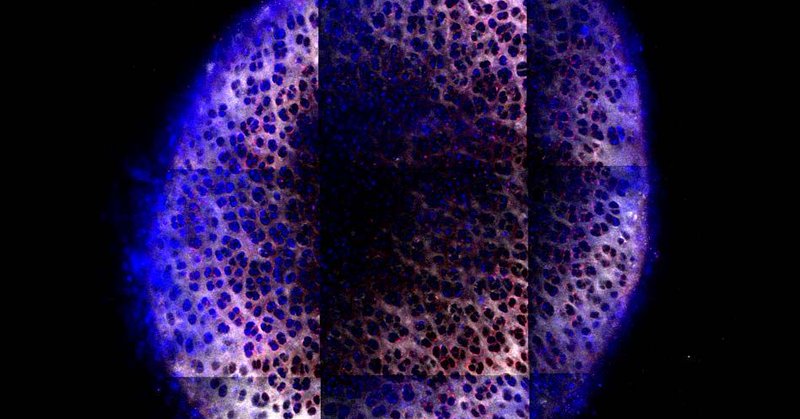

In our recent work with @BUCollegeofENG and @BrookhavenLab at @Nature MicroNano ( https://t.co/1mllrXrCFk), we observe nanostructure of engineered cardiac tissue using synchrotron X-rays, a technique which has potential for live imaging! #cardiactissueengineering #biophysics

Check out our recent publication on a new biomagnetic sensor, which was awarded the journal cover at Nature Microsystems and Nanoengineering! Gen2 designs are in the works. https://t.co/c0H7Fom198